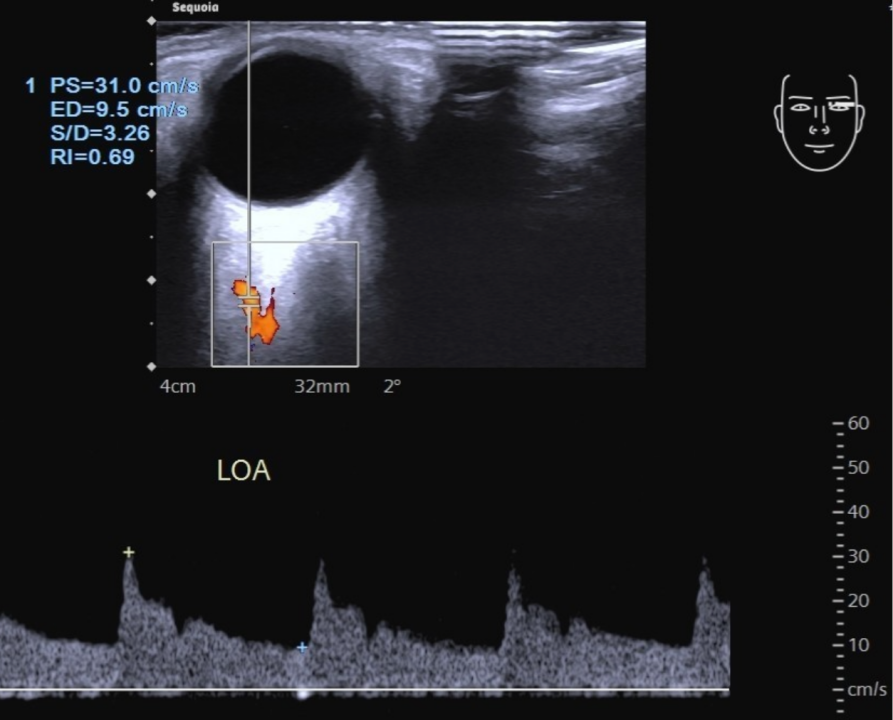

第 3 段眼动脉绕过视神经向前行走于视神经鼻侧,并分出其末支。频谱多普勒显示眼动脉为直角三角形,且呈三峰两谷型,峰速在 30 ~ 40cm/s。

(2)血流速度 计量单位是c m/s,包括峰值流速(p e a ksystolic velocity, PSV)、平均血流速度(mean velocity,MV)、舒张期末流速(endof diastolic velocity,EDV)。TCD与TCCD血流速度正常参考标准下表。其中MV可以是检测仪自动计算, 也可以公式计算:MV=(PSV-EDV)/3+EDV。

(4)血管搏动指数(PI)和血管阻力指数(RI) PI和RI是评价颅内动脉血管阻力的指标,其计算公式为P I=(P SVEDV)/MV,RI= (PSV-EDV)/PSV;常规TCD或TCCD检测分析以PI指数更为准确,正常颅内动脉的PI值为0.65~1.10。